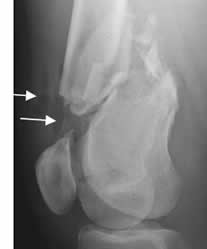

Rx AP. Fractura subtrocantérica de la cabeza femoral, con desviación medial del fragmento distal.